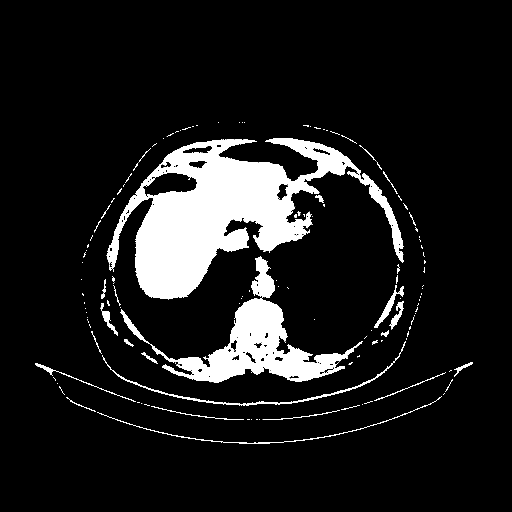

Original NATIVE CT scan (input)

Full window (WL 1023.5, WW 4095 β†’ Low βˆ’1024, High +3071)

Actual HU range: [-1024.0, 3071.0]